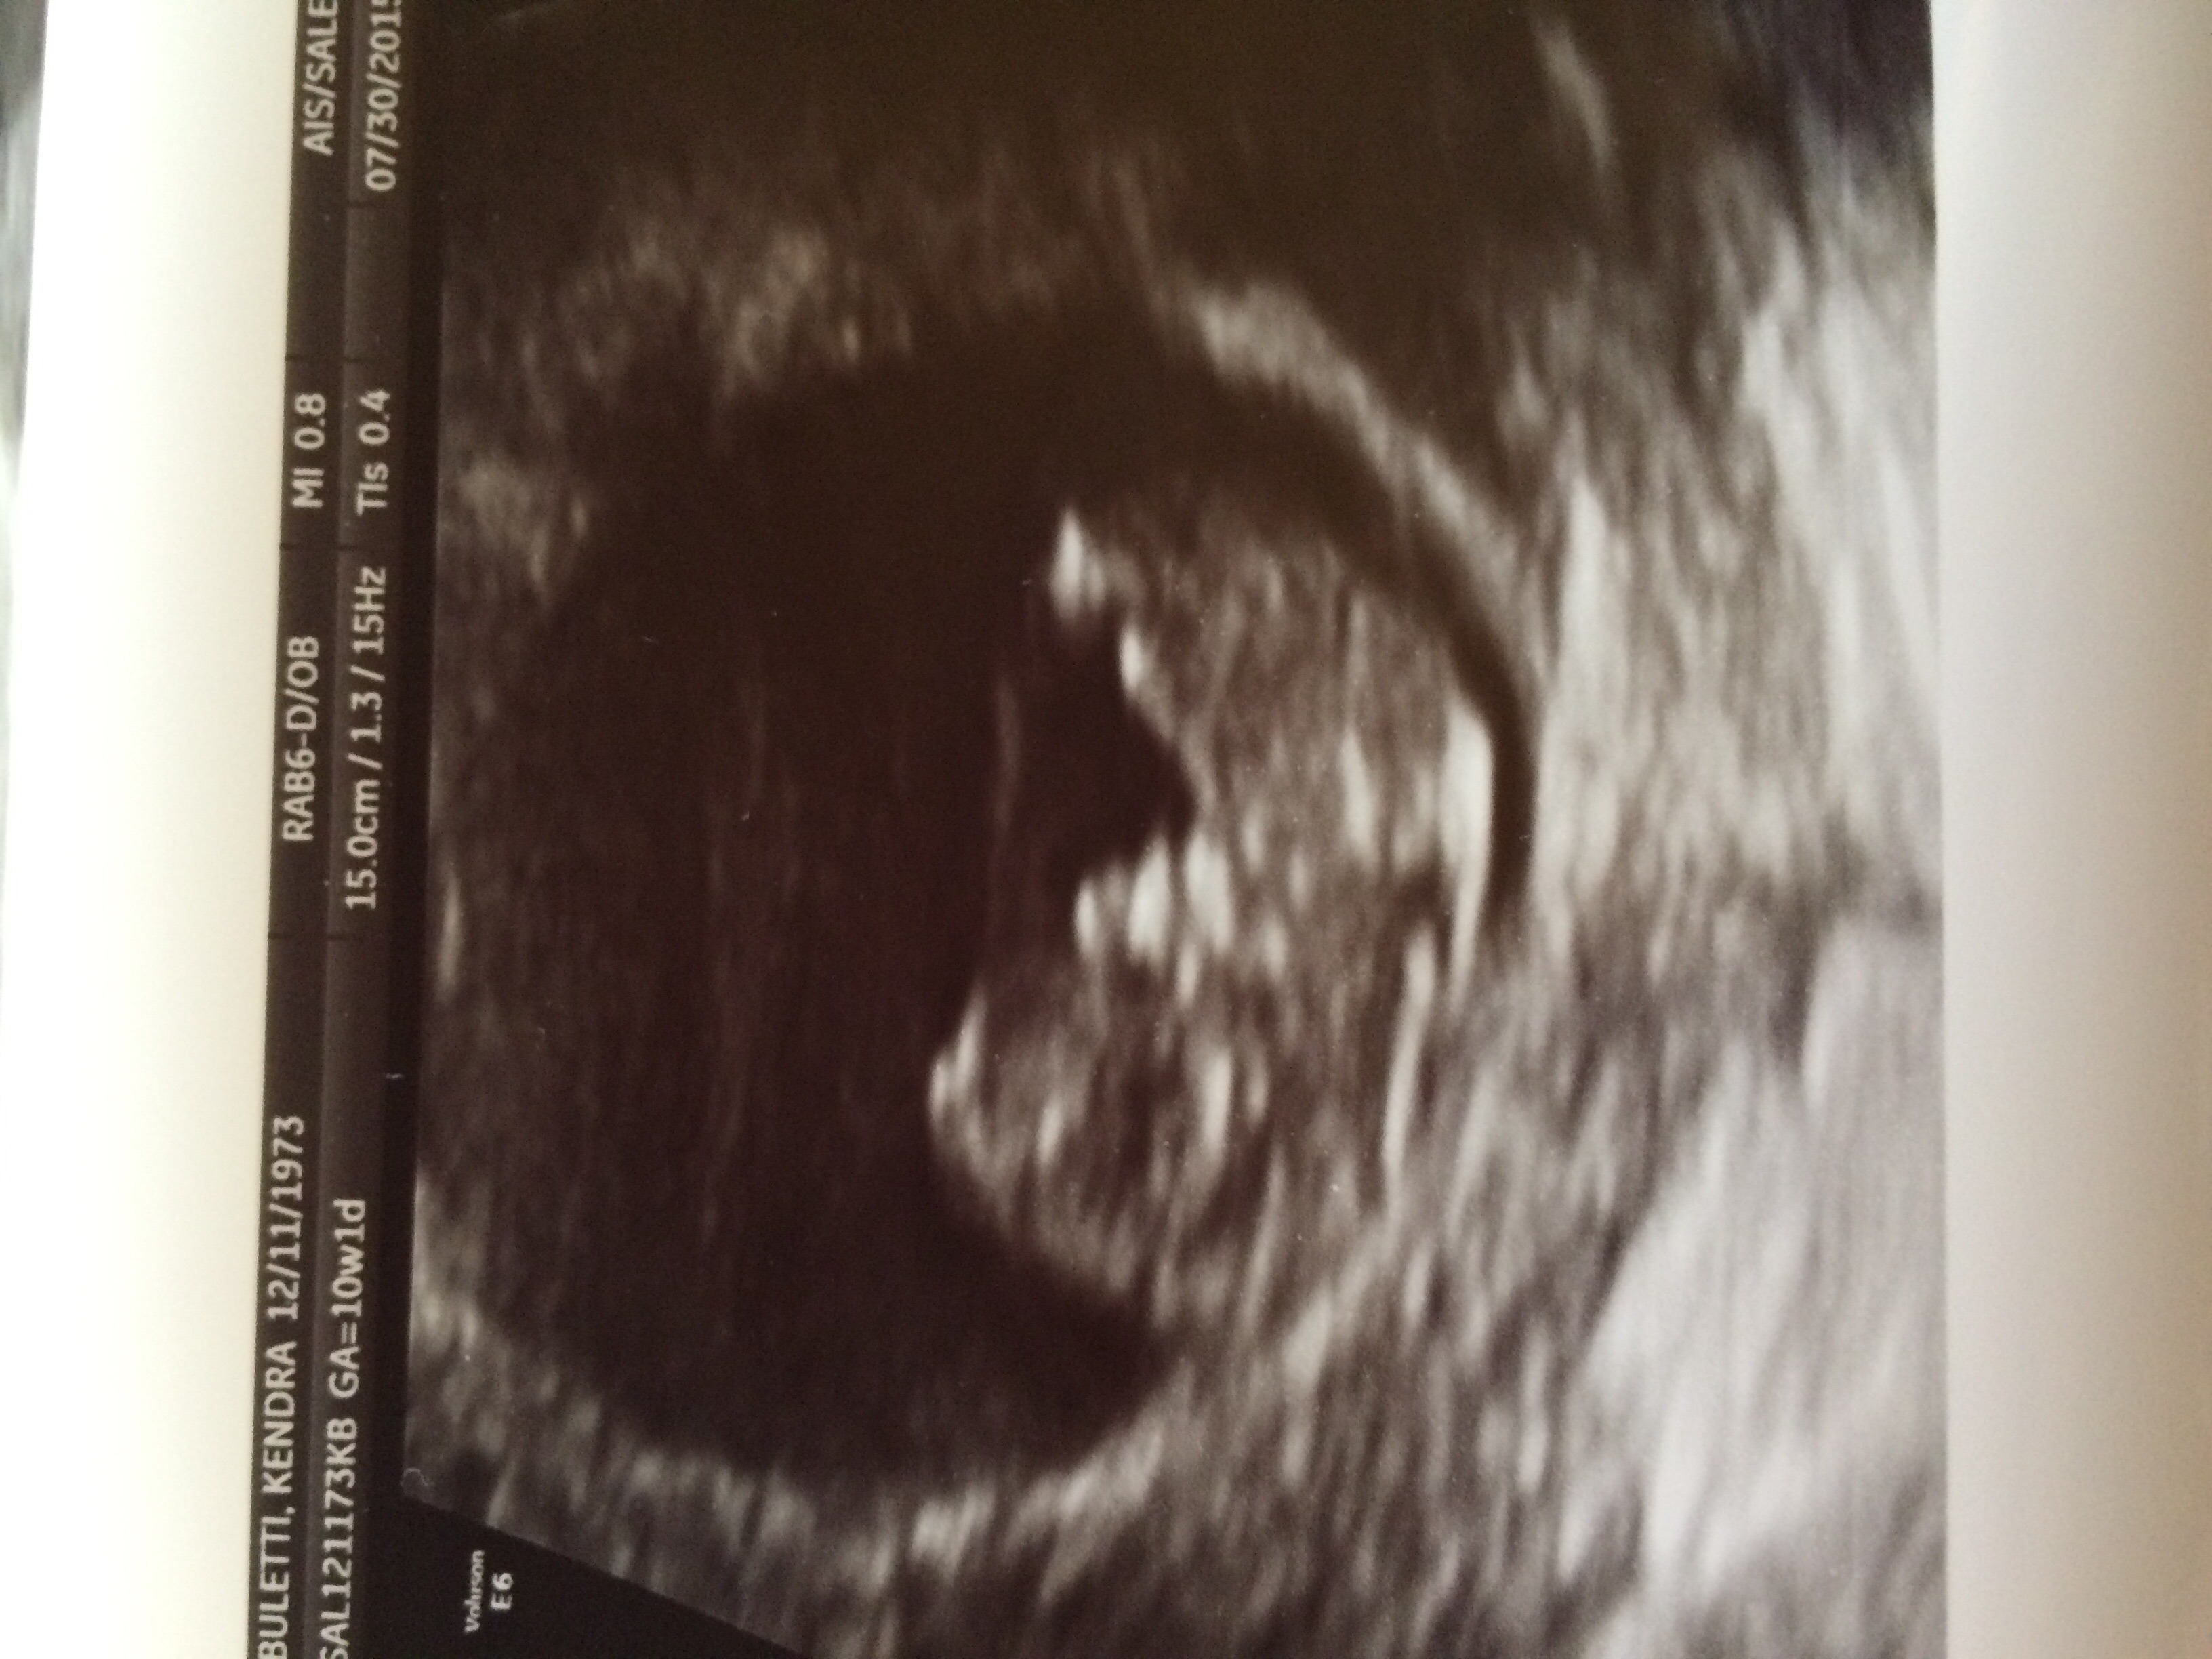

Went for 10wk check up today. Baby is right on schedule and her heart rate is 172 and decided to do a little dancing for the camera today. It was so amazing!